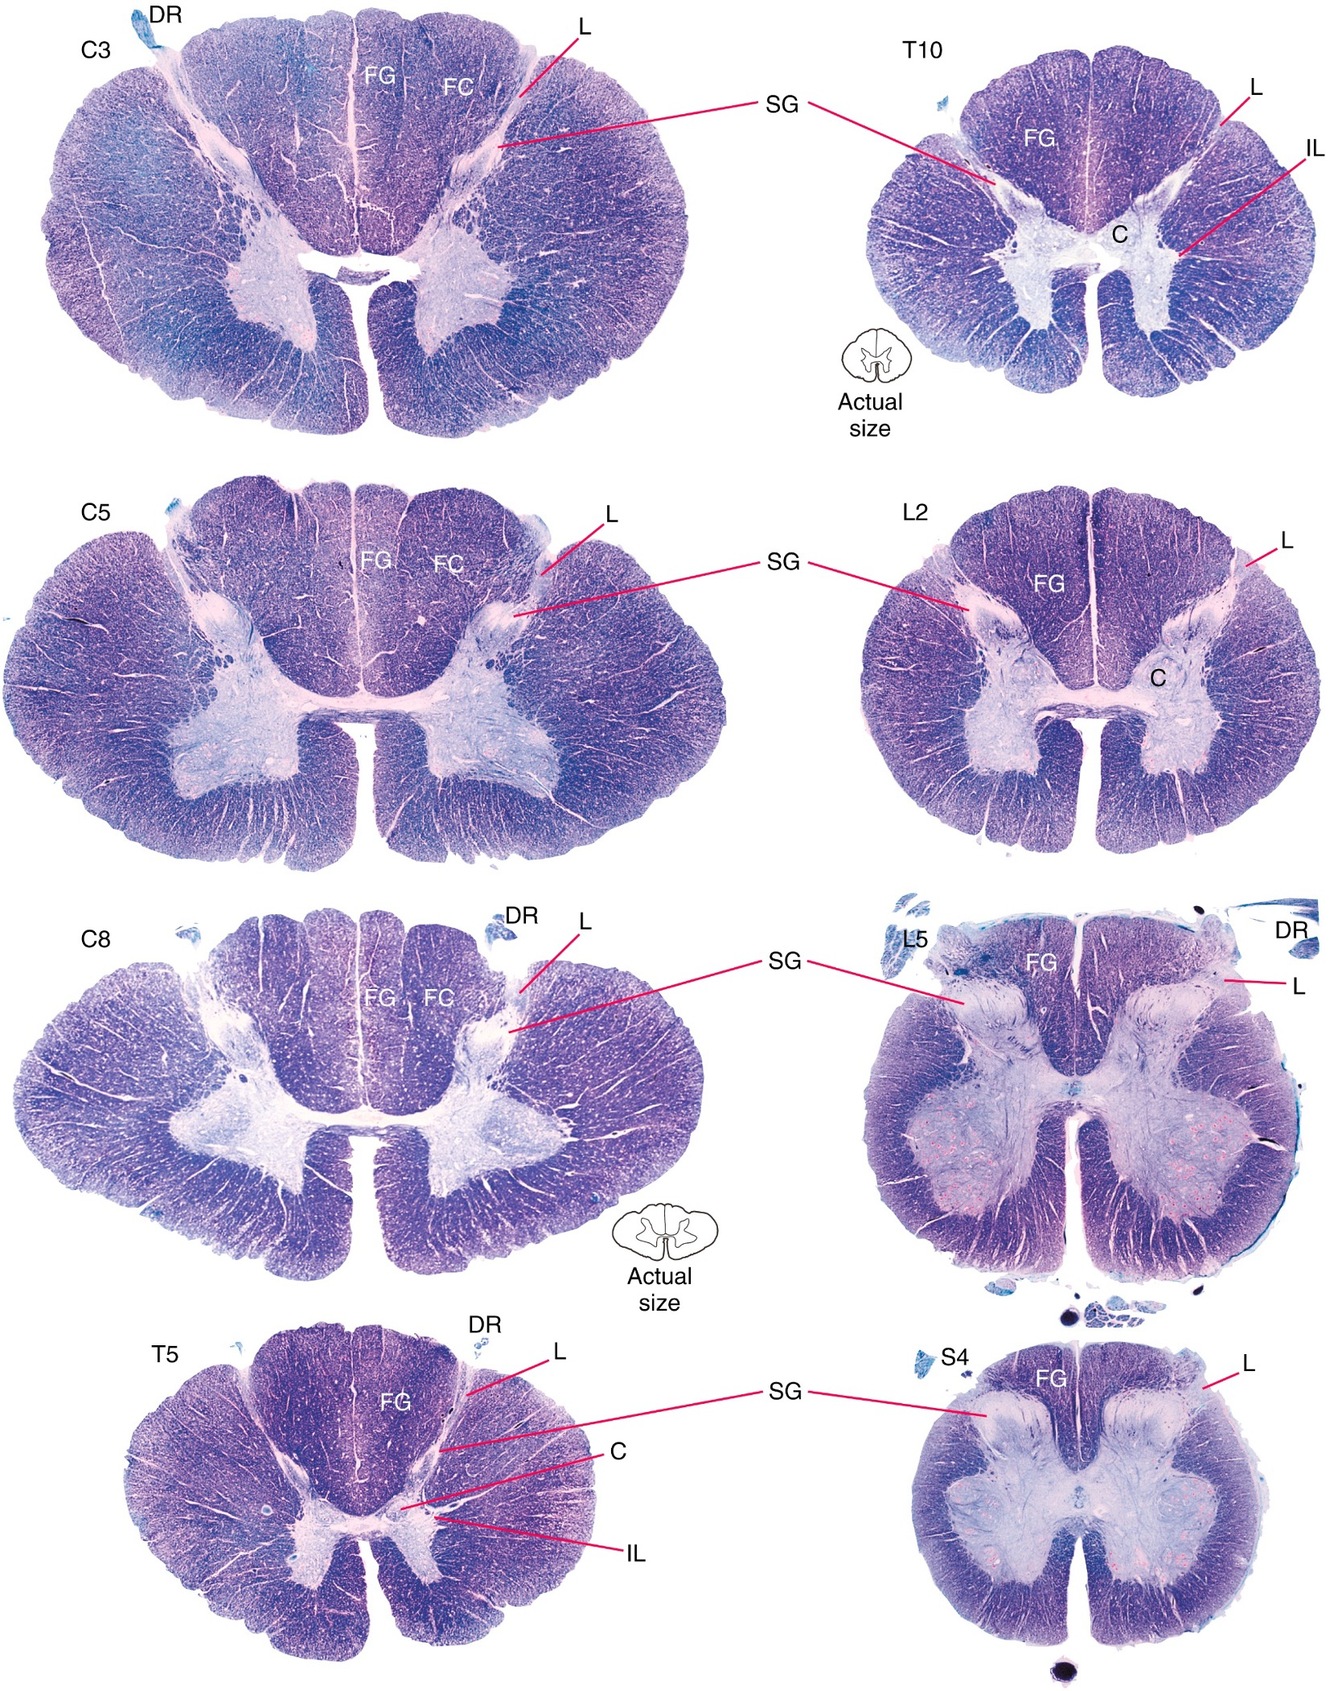

Explain the cross-sectional structure of the spinal cord.

Cross-section of spinal cord at any level is roughly H-shaped – the H being formed by gray matter.

In a cross section:

Gray matter

Divided into horns – usually anterior and posterior

Lateral horn exists in thoracic region (T1-L2)

Also known as intermediolateral cell column

White matter

Divided into funiculi – anterior, lateral, and posterior.

Central canal

Filled with CSF.

Grooves/fissures:

Anterior median fissure

Posterior median sulcus

Posterolateral sulci (on each side)

Does the amount of grey matter vs white matter differ throughout the spinal cord?

YES